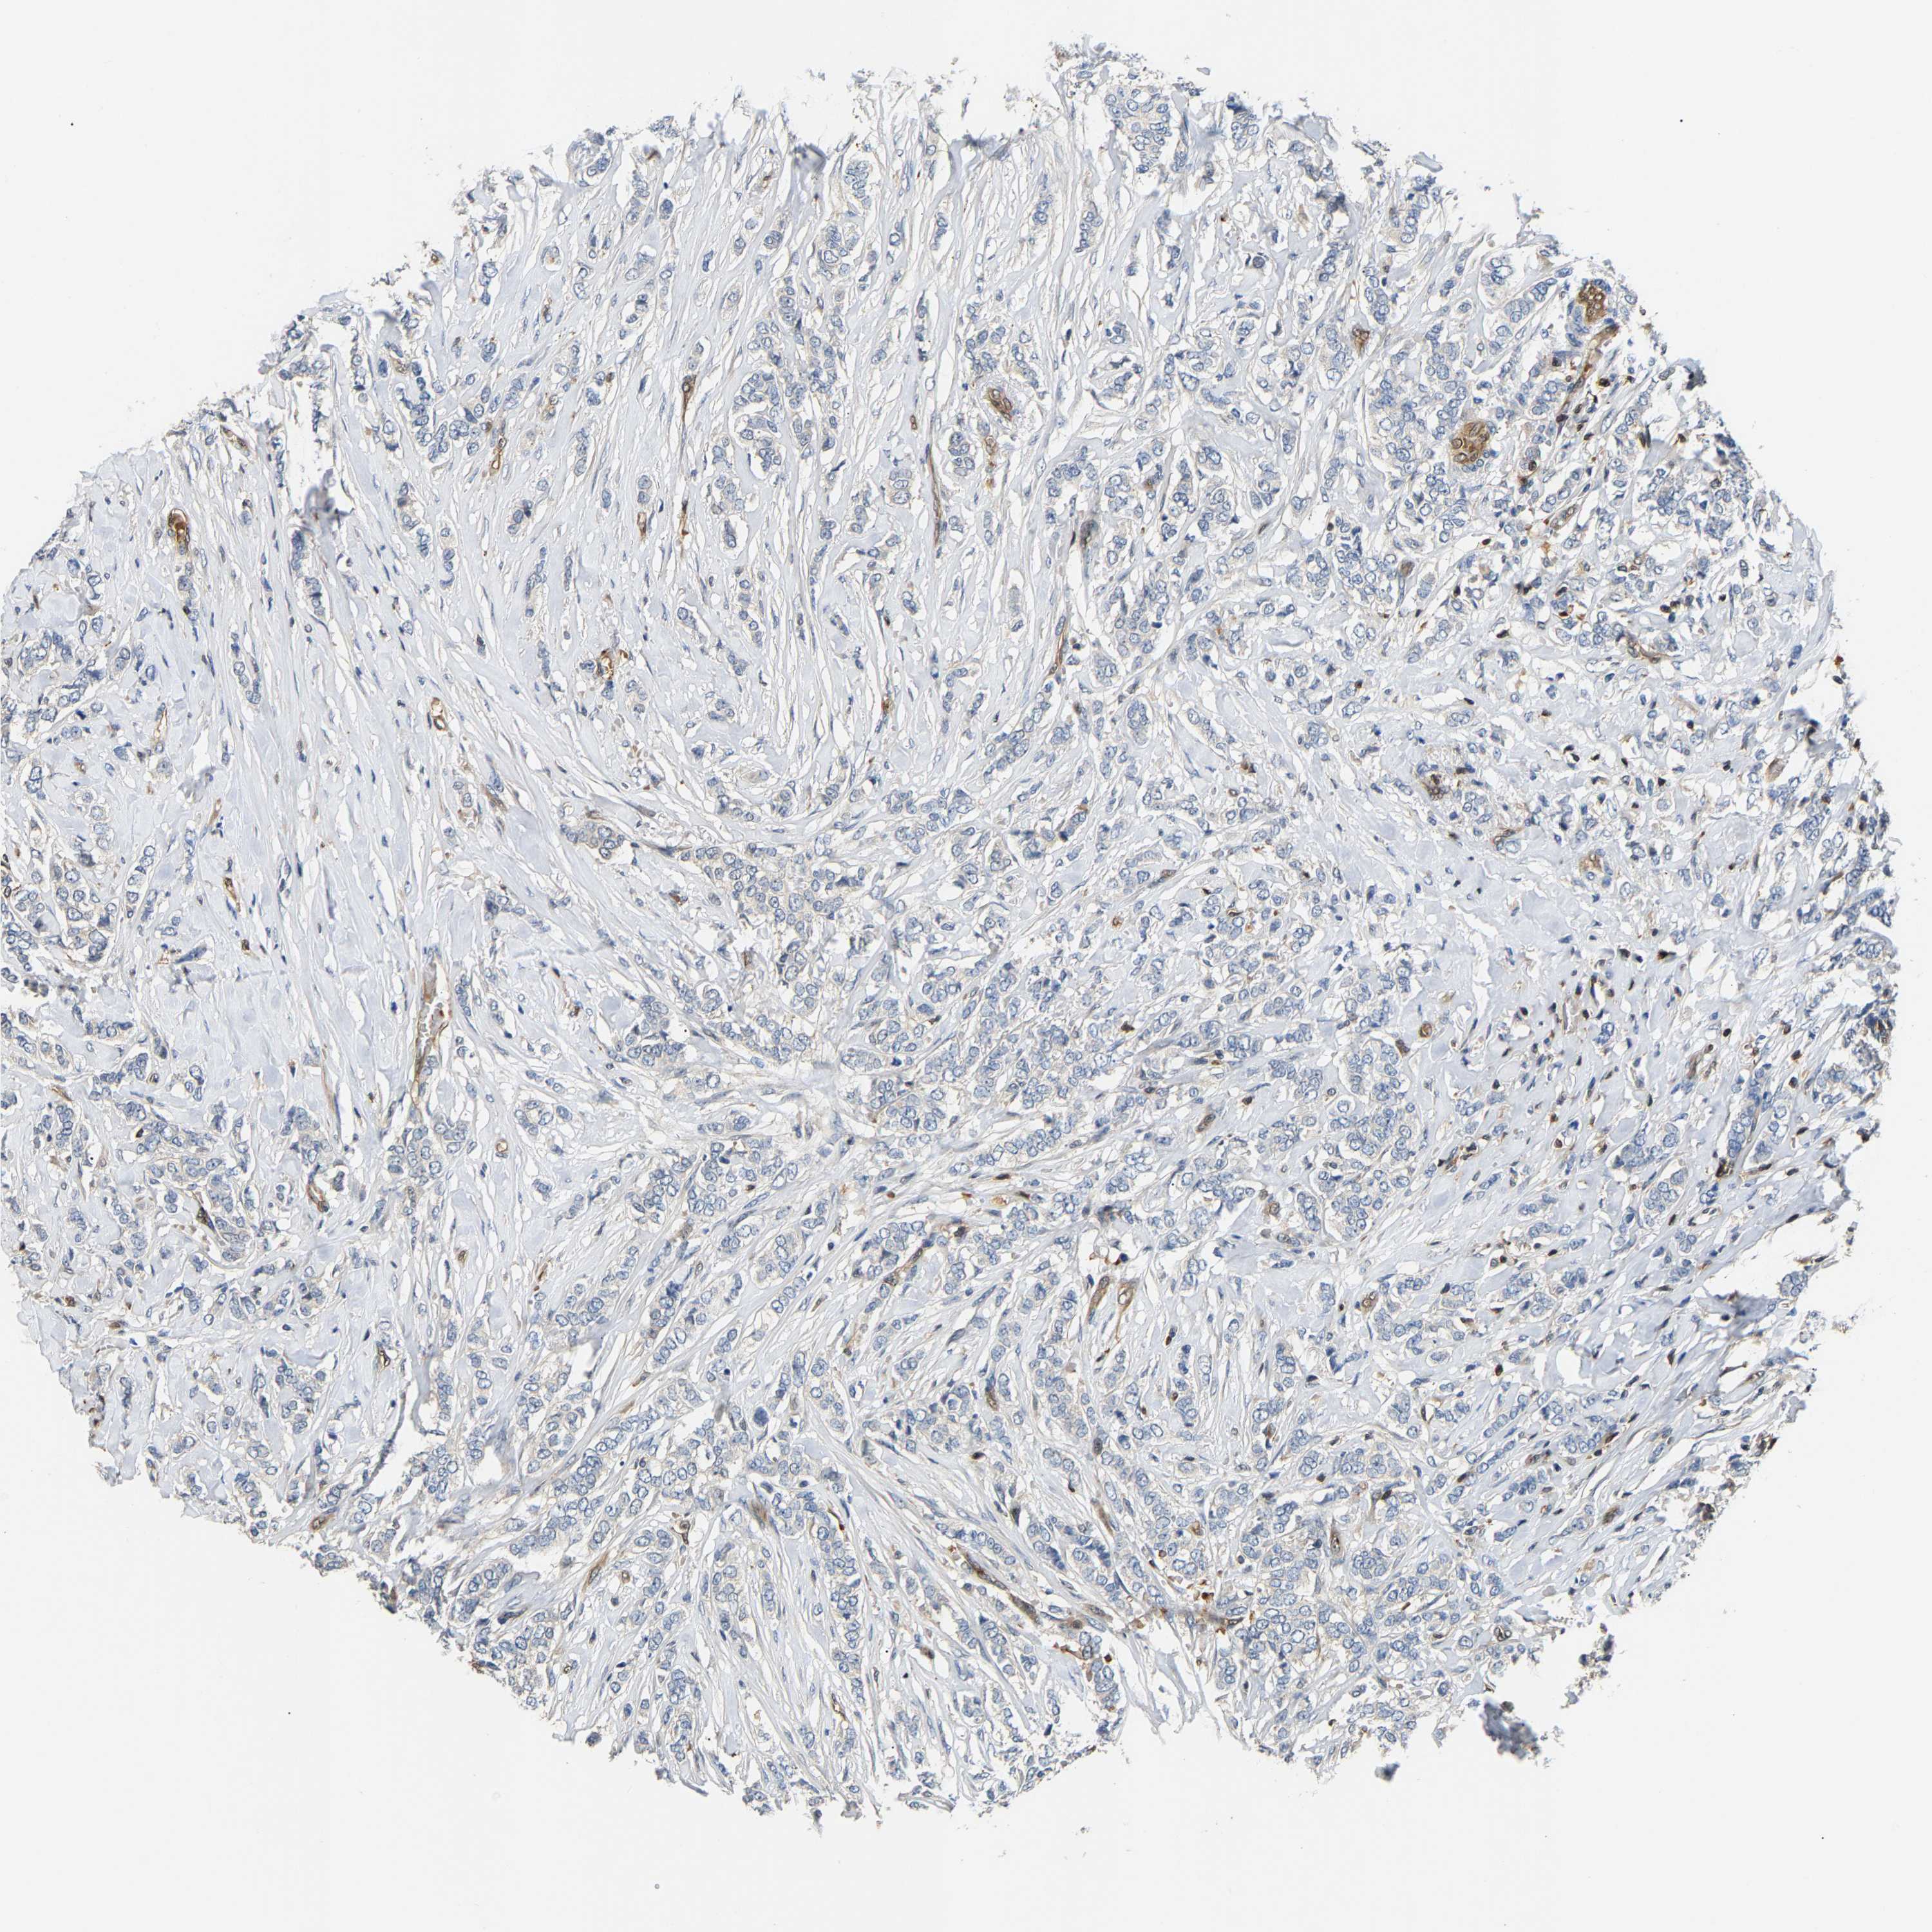

CANCER BREAST CANCER Show tissue menu

BRCA TCGA BRCA VALIDATION PROTEIN EXPRESSION